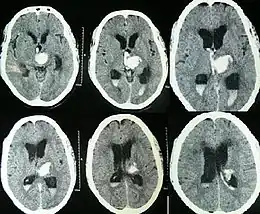

![]() | |

| Hydrocephalus as seen on a CT scan of the brain. The black areas in the middle of the brain (the lateral ventricles) are abnormally large and filled with fluid. | |